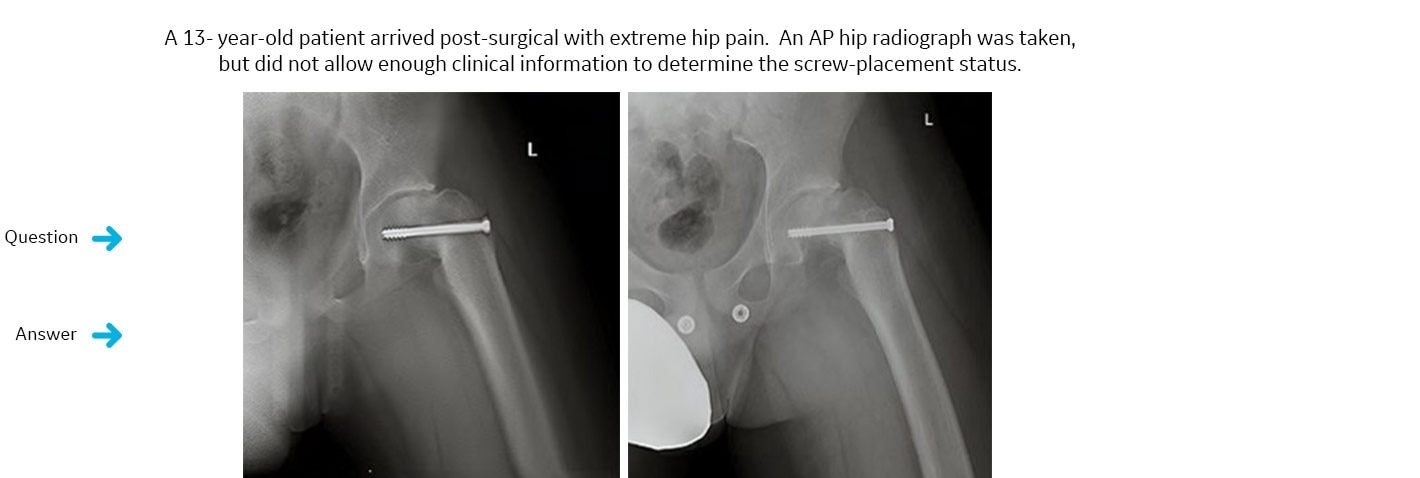

War eine implantierte Schraube in den Bereich des Hüftgelenks eingedrungen?

Eine VolumeRAD-Untersuchung wurde angeordnet. VolumeRAD ermöglichte die Entfernung der überlagernden Strukturen und somit eine sichere Diagnose.Die definitive Antwort: Nein.

Ein Einzelschicht-Intervall der VolumeRAD-Daten zeigte auf, dass die implantierte Schraube nicht in den Gelenkraum eingedrungen war. Der Patient wurde einem sekundären Eingriff unterzogen, bei dem die ordnungsgemäße Platzierung des Implantats sichergestellt wurde.